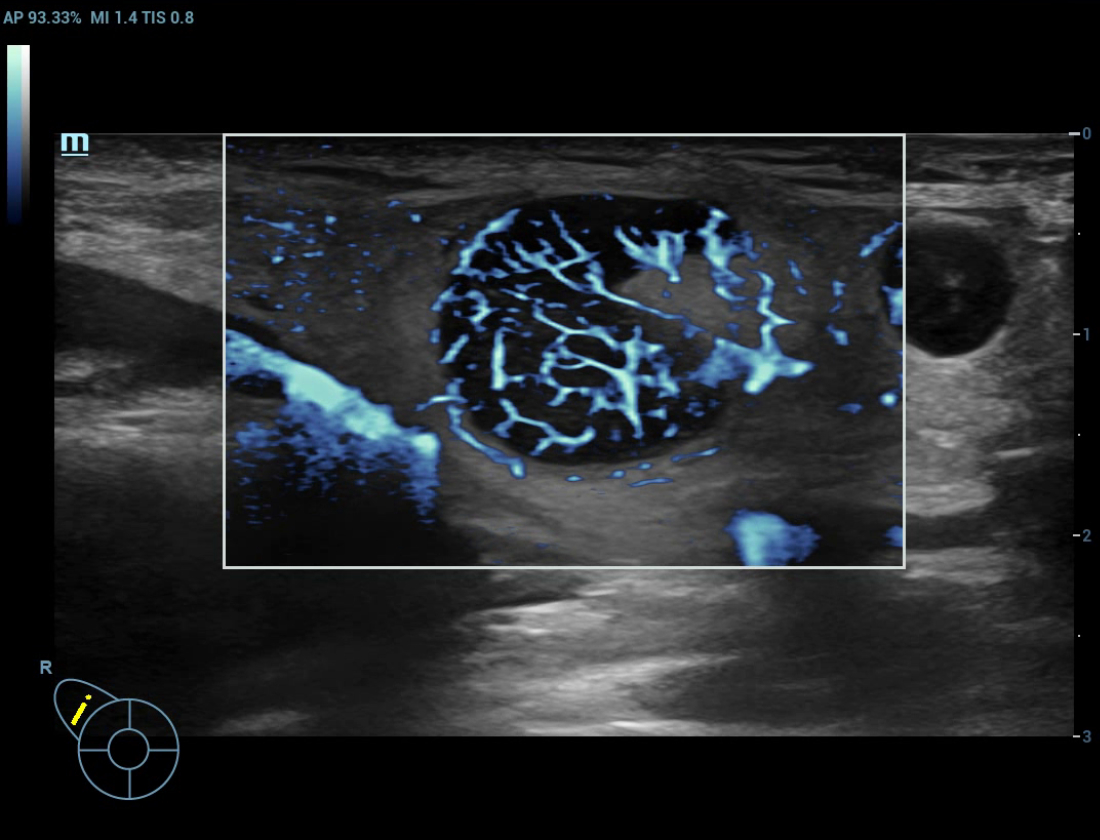

Angiografia ultramicroscû°pica (Ultra Micro Angiography, UMA)

UMA aumenta a confian?a diagnû°stica ao expandir a visibilidade dos fluxos sanguûÙneos atûˋ o nûÙvel de vasos minû¤sculos, com sensibilidade e resolu??o superiores.

sUMA ã C?ncer de tireoide

Galeria de imagens